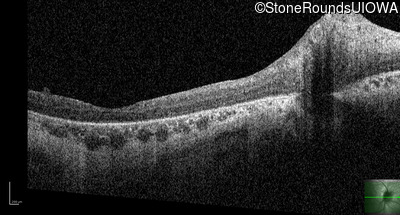

Optical Coherence Tomography - Right - 10/300 sc

Exemplar / OCT Stack